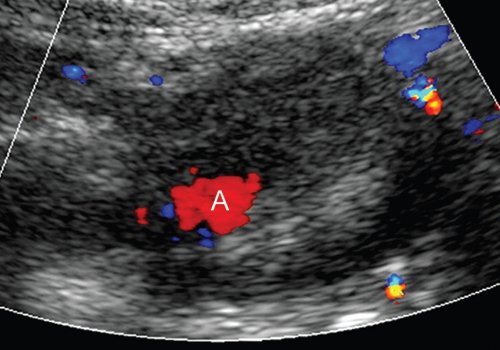

При комплексном УЗИ в В-режиме визуализировали округлое образование в капсуле различной степени выраженности, неоднородное по структуре, по периферии преимущественно эхоплотное с наличием анэхогенной полости, интимно прилежащей к одной из стенок с нарушением ее целостности. При дуплексном сканировании отмечено спонтанное контрастирование полости аневризмы (аналогично и в режиме Sie-flow) с регистрацией артериального кровотока. В режиме импульсной допплерографии линейная скорость кровотока на входе в аневризму была повышена на 18,9-37,8% по сравнению с нормальными значениями с высокой диастолической составляющей. В 18 случаях полость аневризмы окрашивалась не полностью, имелись пристеночные неокрашиваемые участки, которые соответствовали "свежим" тромботическим массам (рис. 1).

Режим ЦДК: AL - селезеночная артерия, CYST - постнекротическая киста.

При комплексном УЗИ, включавшем исследование в В-режиме и дуплексное сканирование висцеральных сосудов и образования, в проекции головки железы определялось образование округлой формы размером 37,6х40,8х54,9 мм, с нечеткими, ровными контурами, по структуре неоднородное, с наличием эхоплотной неравномерно выраженной периферии, преимущественно по переднему и медиальному контурам (тромботические массы) и анэхогенной (жидкостной) полостью по латеральному контуру размером 23,0х15,4 мм. В режиме ЦДК и ЭОДС полость полностью окрашивалась (рис. 7), регистрировали двунаправленный артериальный кровоток (ЛСК до 0,5-0,6 м/с).

Режим ЦДК: A - аневризма, CONF - конфлюенс воротной вены, V - венозные коллатерали.